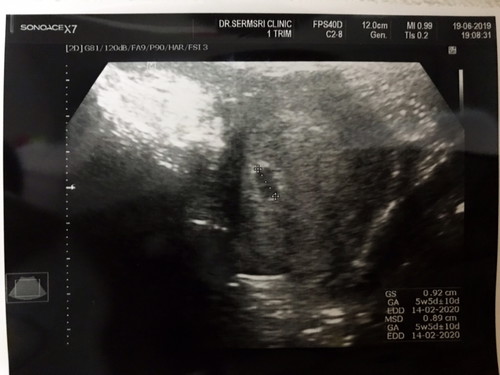

ขอดูภาพเบบี๋ที่เป็นถุงตั้งครรภ์

ของแม่ๆหน่อยค่า วันนี้ปวดหน่วงๆท้อง เลยไปให้หมออัลตราซาวด์ ดู เห็นแต่ถุงตั้งครรภ์ หนูยังจิ๋วอยู่ใช่ไหมคะ เลยมองยังไม่เห็นหัวใจ. 5 week 5day ประมาณไหมคะแม่ๆ